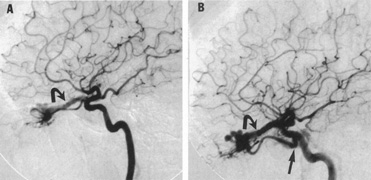

In some persons, the cavernous sinuses have existing or potential connections to the deep venous system of the brain. Indeed, this may be the preferential route of venous drainage from all or part of the cavernous basal sinus complex. Therefore, the clinical appearance of orbital venous hypertension associated with a cavernous dAVM may be relatively minimal, but arterialized flow is transmitted instead chiefly via venous dural channels draining the medial aspects of the temporal lobes and the basal vein of Rosenthal. The latter drains an extensive deep parenchymal territory, including part of the posterior fossa. This effluent pattern explains how some cavernous dAVMs or CCFs present with relatively minor outward physical signs but with serious complications from cortical venous hypertension (Fig. 18), elevated intracranial pressure (a form of secondary pseudotumor cerebri syndrome; see Chapter 5, Part II), temporal lobe seizures, brain parenchymal hemorrhage caused by venous infarction or venous rupture (Fig. 19), or edema of the posterior fossa structures.119

Fig. 18. A 25-year-old man developed severe right-sided proptosis and a loud bruit at the time of a vehicular accident. Lateral projection of the right internal carotid artery in the early arterial phase (A) and late arterial phase (B) in anteroposterior projection demonstrate immediate opacification of the superior and inferior ophthalmic veins (straight arrows), the inferior petrosal sinuses (curved arrows) and of the deep parenchymal veins of the right hemisphere (open curved arrows). The fistula was related to a large carotid laceration involving the cavernous and supraclinoid segments of the right internal carotid artery. The artery could not be preserved at the time of treatment. C: Latex balloons (open-ended arrowheads) were placed in the fistula and within the carotid artery at the time of treatment. (Courtesy of Frank Huang-Hellinger)

Fig. 19. A 30-year-old woman presented with headaches. Lateral views of left (A) and right (B) internal carotid arteriograms demonstrate developmental venous malformation of the cribriform plate supplied by both ophthalmic arteries. Note subarachnoid veins of the anterior cranial fossa (curved arrows). In addition, the right ophthalmic artery (B) has a cavernous origin (arrow), a vestige of the dorsal ophthalmic artery that usually atrophies in fetal development.

The anatomic substrate for the vascular chain of complications can be defined best by timely conventional selective angiography alone, even in patients presenting with seemingly mild signs. The decision to intervene and the mode of treatment can only be based on the precise angiographic details.

Endovascular treatment of fistulous lesions in the cavernous sinus can be pursued via transarterial or transvenous routes.114,115,122–124 In the case of direct CCFs, the laceration of the carotid artery is usually most easily sealed with a transarterial detachable balloon (see Fig. 17).125 If possible, this technique is performed by detaching the balloon on the venous side of the fistula to close it, while preserving flow in the carotid artery. Occasionally, such precise balloon positioning may not be possible or the laceration of the carotid artery might be complex. Therefore, assuming that adequate collateral intracranial circulation has been demonstrated, a trapping procedure using detachable balloons may be necessary, that is, closing the carotid artery above, below, and at the site of the fistula. Detachable balloons are manufactured from silicone or latex and their placement can be difficult, sometimes requiring a shift in midprocedure to alternative techniques. Spontaneous deflation over a period of weeks occurs in both types of balloon when the inflating material is conventional radiographic contrast. By this time, however, it is hoped that the fistula site will have thrombosed and become endothelialized. Therefore, delayed recanalization of the fistula site after balloon closure is not a common problem, although these sites have a 20% to 30% rate of pouch or pseudoaneurysm formation on delayed follow-up.114 However, clinical sequelae of these pouches or pseudoaneurysm sites seem to be uncommon.